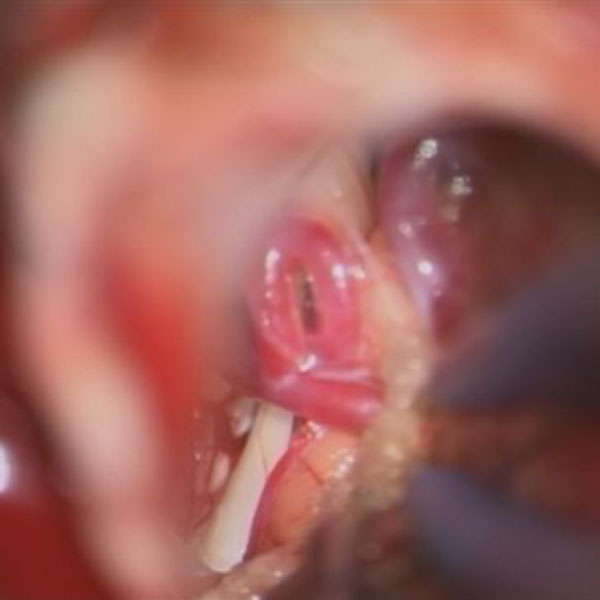

手術中

処置前

処置後